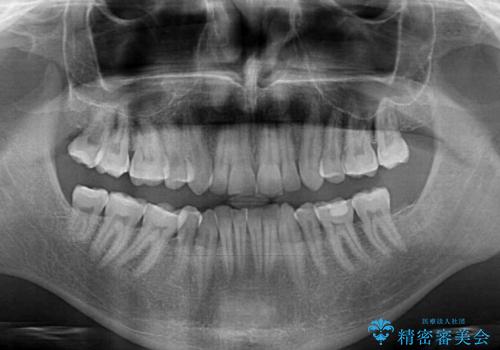

- 上下前歯の叢生を気にして来院された患者様です。

抜歯矯正をした後戻りということで、歯列不正はそれほど大きくなかったため、インビザライン・ライトを用いて矯正治療を行うこととしました。

前歯のデコボコが残っており、シミュレーション通りに動いていない部分がありましたが、再矯正であることやご本人の満足いくところまでデコボコが改善されたとのことで、治療を終了することとしました。